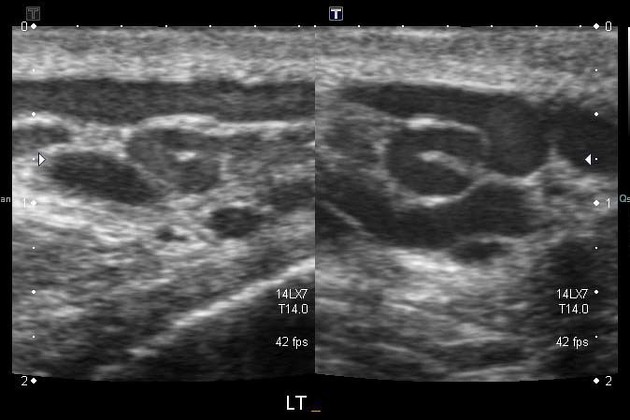

- Skrotal ultrasonografi